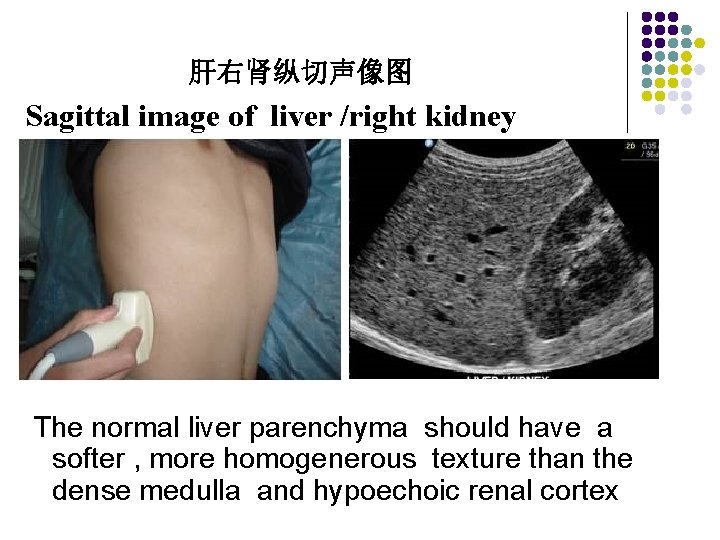

Longitudinal Scan Plane l Scan Ⅳ, Ⅴ, Ⅵ The nest three scans should be made in small increment through the right lobe of the liver. The last scan is usually made to show the right kidney and lateral segment of the right lobe of the liver. The liver texture is compared with the renal parenchyma. The normal liver parenchyma should have a softer , more homogenerous texture than the dense medulla and hypoechoic renal cortex. Liver size may be measured from the tip of the liver to the diaphragm. Generally this measurement is less than 15 cm, with 15 to 20 cm representing the upper limits of normal. Hepatomegaly is present when the liver measurement exceed 20 cm.

肝右肾纵切声像图 Sagittal image of liver /right kidney The normal liver parenchyma should have a softer , more homogenerous texture than the dense medulla and hypoechoic renal cortex

The last scan is usually made to show the right kidney and lateral segment of the right lobe of the liver. The liver texture is compared with the renal parenchyma. The normal liver parenchyma should have a softer , more homogenerous texture than the dense medulla and hypoechoic renal cortex.